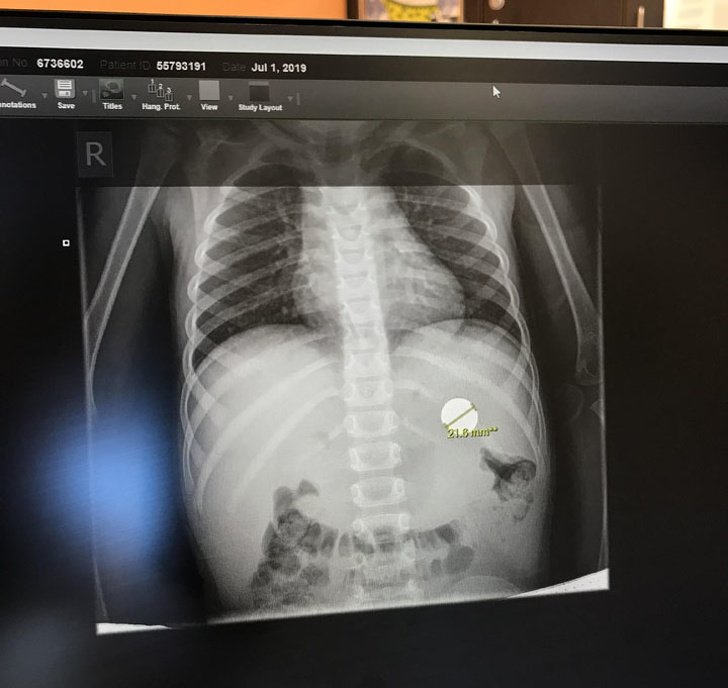

“Meu sobrinho engoliu uma moeda”